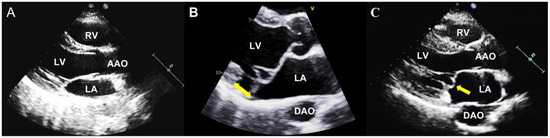

In anatomical studies, the normal mitral annulus is always described as a ‘D-shaped’ structure, with the anterior and posterior mitral valve leaflets inserted [31,32]. However, scientists have noticed an abnormal attachment of the posterior leaflet, which is directly on the atrial wall, called MAD [33,34]. Through further studies, MAD has been described as an anomalous detachment of the mitral annulus from the myocardium of the basal left ventricular free wall, accompanied by an atypical systolic excursion of the leaflet hinge point of the posterior reaching into the LA [33,34,35,36] (Figure 1). The mitro-aortic fibrous continuity linking the anterior mitral leaflet and the aortic cusps restricts the circumferential extension of MAD. Therefore, MAD is only observed at the insertion of the posterior leaflet, and this abnormal disjunction extends laterally in a variable manner beneath all scallops of the posterior leaflet, with a notable emphasis on the central posterior scallop [37,38].

Figure 1.

The mitral valve with and without MVP. (A) The parasternal long-axis view shows a normal mitral valve apparatus; (B) The parasternal long-axis view shows an MVP with MAD (yellow arrow); (C) The parasternal long-axis view shows an MVP without MAD (yellow arrow). LA: left atrium, LV: left ventricle, RA: right atrium, RV: right ventricle, AAO: ascending aorta, DAO: descending aorta, MAD: mitral annular disjunction.

Echocardiography can be used to diagnose MVP, follow up, and evaluate whether to intervene [11], which is the foremost and frequently employed imaging modality for MVP (Figure 1). MVP represents an abnormal systolic change in the mitral valve as a displacement of one or both of its leaflets at more than 2 mm concerning the plane passing through the mitral valve annulus, superiorly into the LA, which can be evaluated in the parasternal long-axis or the apical 3-chamber view on 2D transthoracic echocardiography (TTE) [67,68,69].